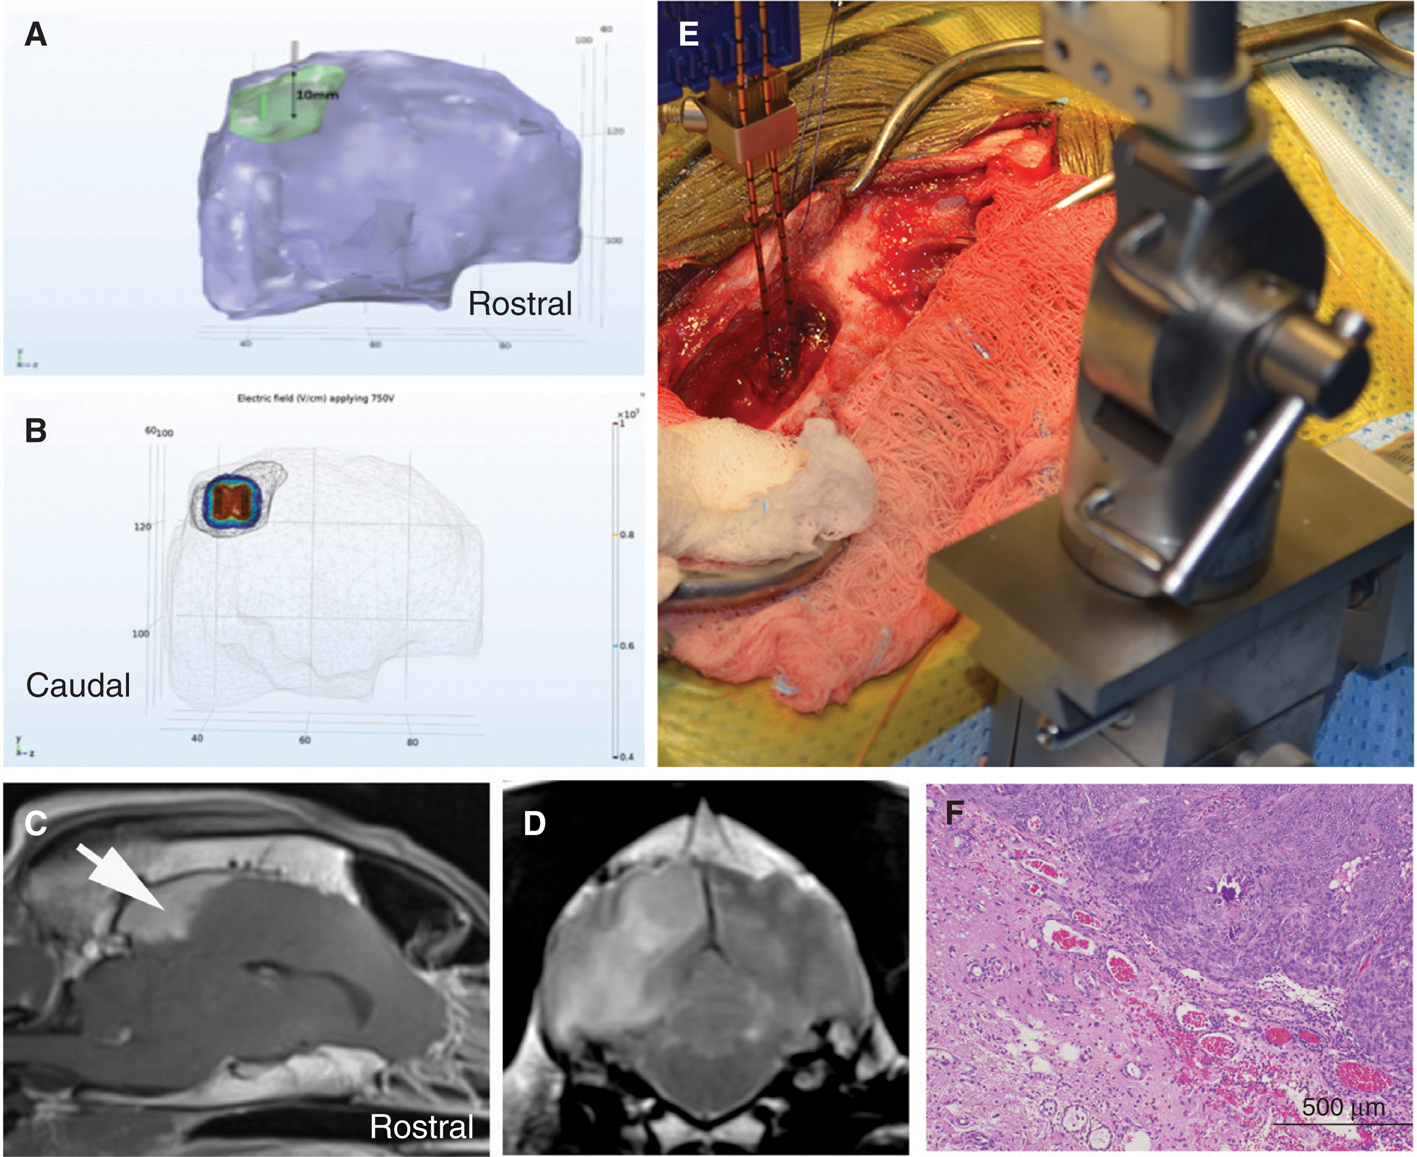

We have evaluated the safety and preliminary efficacy both IRE (Figure 3) and H-FIRE (Figure 4) in dogs with spontaneous brain tumors (77, 79, 86). An integral component of the preclinical evaluation of IRE and H-FIRE was the development of anatomically accurate numerical treatment planning models that maximize tumor coverage while minimizing damage to surrounding healthy tissue and also account for the increase in tissue conductivity that occurs during pulse delivery (8688). Incorporating therapeutic plans developed from patient-specific, segmented medical images imported into finite element analysis modeling software, we have confirmed the ability of IRE and H-FIRE to safely and precisely ablate normal and neoplastic canine brain tissues with a submillimeter line of demarcation between ablated and non-treated tissues (79, 86, 89). IRE treatment of canine gliomas resulted in significant objective tumor responses in 4/5 dogs with quantifiable target lesions (Figure 3), and these radiographic responses were accompanied by improvements in Karnofsky performance scores and posttreatment seizure control (72, 86). Similarly, using a treat and resect treatment paradigm, we have confirmed the ability of H-FIRE to safely and precisely ablate clinically relevant volumes of canine brain tumors without the induction of muscular contractions during pulse delivery (Figure 4).

Fig 4

Figure 4 High-frequency irreversible electroporation (H-FIRE) treatment of a canine Type I parasagittal meningioma. Treatment planning (A, B) involves segmentation of the tumor (green) and brain (purple) from the patient’s MR images (C, D), and determination of the electrode placement trajectory (A). The resulting electric field distributions are then simulated (B) using finite element analysis software (B). The H-FIRE electrodes are placed using intraoperative stereotaxy (E) according to the treatment plan, and the pulses delivered. After-HFIRE treatment, the tumor was resected and serially sectioned to correlate the predicted with actual ablation volume. Photomicrograph of the treatment margin (F), illustrating a sharp line of demarcation between H-FIRE ablated (lower left) and viable tumor (upper right); H&E stain.

To overcome previously recognized barriers to the translation IRE and H-FIRE therapies to the clinic, such as the inability to incorporate MR image-guidance into treatments and need to use multiple software programs for therapeutic planning, we have been developing a comprehensive solution that combines all of the necessary components of the workflow in a user-friendly platform that can be incorporated into contemporary neurosurgical theaters (86, 90, 91). The foundation for this platform is an open-source, online interface that uses a treatment planning approach similar to that employed in radiotherapeutic applications. The software allows for tissue-specific segmentation, determination of the tumor dimensions, and formulation of virtual electrode insertion approaches that can be used in surgery (91). These volumetric representations are then used to perform computational simulations of the electric field distribution surrounding the active electrodes during pulse delivery to determine tumor coverage (Figure 4) and cell kill probabilities (90, 92). Validation of the predicted therapeutic outcomes generated with this platform is currently underway using clinical data from IRE-treated dogs with intracranial gliomas (90).